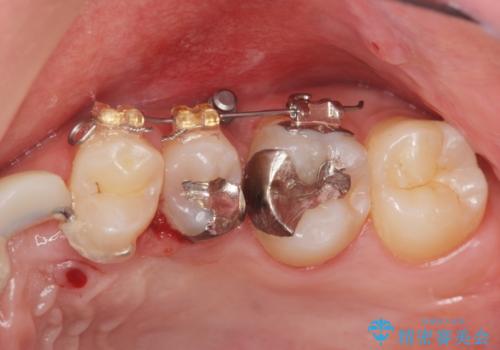

- 部分ワイヤー矯正

- ねじれてしまっている奥歯の矯正治療、銀歯のセラミック治療を求めて来院されました。

銀歯を外す前に部分矯正治療を行うことで歯のポジションを調整したのち、セラミック治療を行います。

90°ねじれてしまっていた歯を、矯正治療で治し、前後の歯の咬合関係も改善してしっかりと噛めるようになりました。